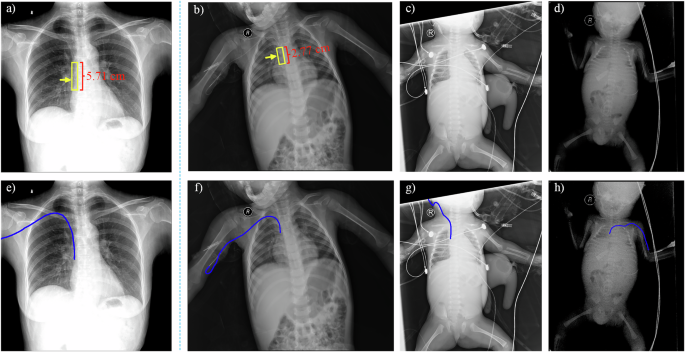

Nonetheless, PICC placement in infants and toddlers presents distinct physiological and behavioral challenges compared to adults10. Anatomical constraints in the pediatric population, including reduced vessel calibers, thin and collapsible venous walls, and diminished vascular compliance, significantly increase puncture difficulty and catheter dislodgement risk. Moreover, procedural distress frequently induces agitation and involuntary movement in these patients, often leading to insertion failure. Extensive research confirms that PICC tip position is a critical determinant of both therapeutic efficacy and complication rates11. Malpositioned tips can lead to severe adverse events, including catheter dysfunction, arrhythmias, cardiac tamponade, thrombotic events, and bloodstream infections12,13. The optimal tip position for an upper extremity PICC is within the lower third of superior vena cava or at the cavoatrial junction14. Notably, the target zone for pediatric tip placement is considerably smaller (only 2.77 cm) compared to that for adults (5.71 cm) (Fig. 1a, b), underscoring the inherent difficulty in achieving correct catheter positioning. Even following successful initial placement, tip migration may occur due to suboptimal venous selection, limb movement, post-flush catheter displacement, hemodynamic changes, or external tissue compression15. Infants and toddlers are at heightened risk of migration owing to movement during crying, which further compromises catheter retention and long-term usability.

Yellow arrows and squares denote the PICC tip position and target zone. Red indicates the length of the target zone. a Standard adult PICC radiograph. b–d Pediatric PICC radiographs demonstrating non-standard positioning, medical device interference, and low-contrast. e–h Corresponding ground-truth PICC labels.

Deep learning has emerged as a widely used approach for medical image segmentation. Current approaches to PICC segmentation consist of coarse-to-fine frameworks18, multi-stage networks19, and multi-task models20. However, these methods are primarily developed for adult populations and fail to accommodate the unique challenges presented by infants and toddlers. These challenges include: (1) Performance degradation in non-routine views: Existing methods perform reliably on standard anteroposterior radiographs that capture dominant thoracic regions (Fig. 1a), but suffer significant performance decline when applied to non-standard projections. Pediatric PICC radiographs are frequently acquired in unconventional views, which often include reduced regions of interest and increased non-thoracic content (Fig. 1b–d), significantly complicating catheter identification. (2) Constrained target zones: The acceptable range for optimal tip placement is exceptionally narrow in infants and toddlers. For example, this target zone spans only 2.77 cm in a typical 2-year-old (Fig. 1b) and becomes even more restricted in children under 2 years old. (3) Interference from medical devices: The presence of life-support and monitoring equipment (Fig. 1c) introduces complex imaging artifacts that often obscure the catheter. (4) Low contrast and resolution limitations: PICCs inherently exhibit low radiopacity against surrounding tissues (Fig. 1d). While modern vascular segmentation methods achieve high accuracy in angiographic studies (e.g., 97.11% accuracy in ref.21), accurate delineation of low-contrast PICC lines remains a technical challenge.